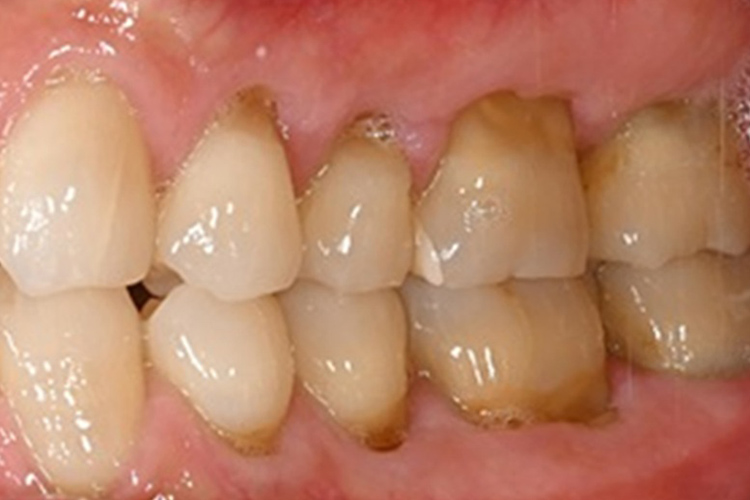

実際の実施例1

この患者様は、口腔内全体において重度の歯周病が生じており、歯磨き指導、クリーニング、Flap手術等を行ったが、歯周ポケットが深すぎるため、ブルーラジカル適用症例と診断し、施術を行いました。

(実施前)

施術前のレントゲンと口腔内写真です。施術前にプラークの除去を行ってから、施術します。